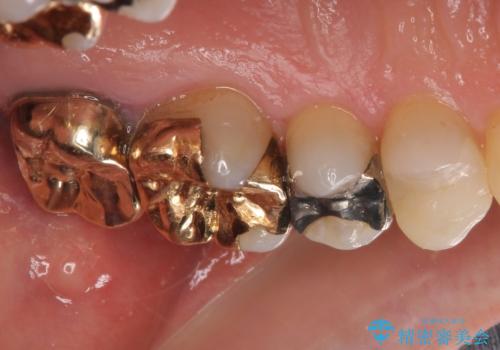

外れてしまった銀歯 セラミックインレーで自然な仕上がりに

- 奥歯の銀歯が外れてしまったため、セラミック治療を希望された患者様です。

セラミックインレーによる修復治療を実施しました。

正面から見える場所であったため、セラミックインレーで自然な口元にすることができました。